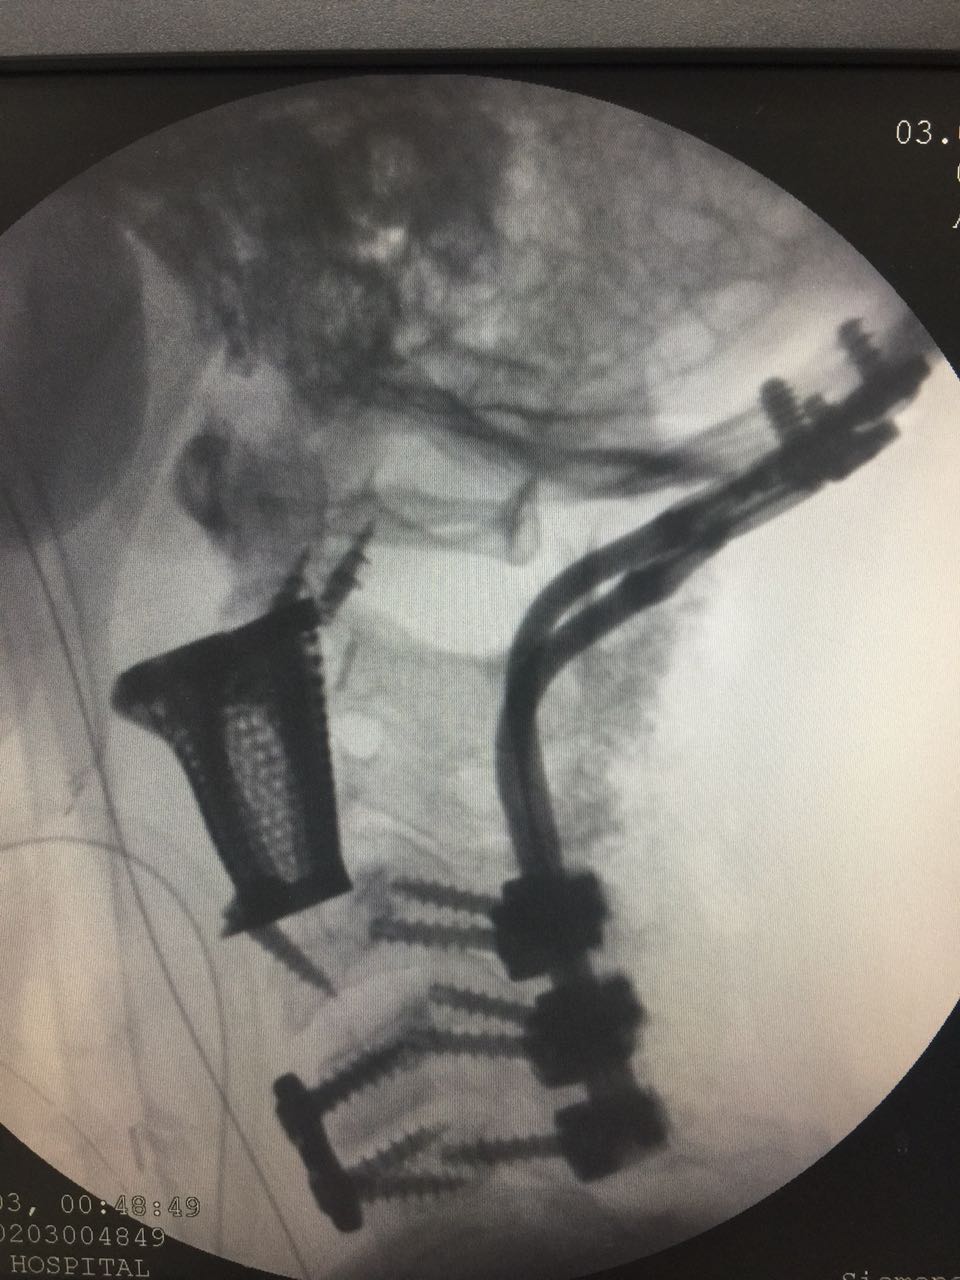

Photo of 3d printed spine of the patient . This was used to measure the gaps between the vertebrae to ensure that the final replacement vertebrae would fit in perfectly. Photo of 3d printed spine of the patient . This was used to measure the gaps between the vertebrae to ensure that the final replacement vertebrae would fit in perfectly.

A team of surgeons at Medanta – The Medcity in Gurgaon, India, managed to get 3d print titanium replacements of her damaged first, second and third vertebrae and insert them in her spine in a 10 hour surgery. CT and MRI scans of the spine were obtained first, which were then studied to ensure that the final, 3d printed vertebrae would fit in perfectly. The 3D printed titanium replacements were also tested for biomechanics and stress risers, and multiple design teams from India, US and Sweden provided the final version of the implants to the hospital where the surgery was performed.